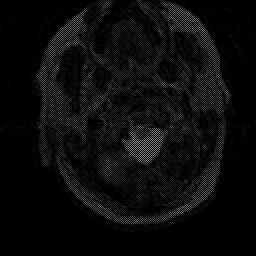

Subacute Stroke, overlay -- Slice #0

[Home][Help][Clinical] Slice 0

Click on sagittal image to select slice. Click on thin tickmark to change timepoint, or thick tickmark for overlay.